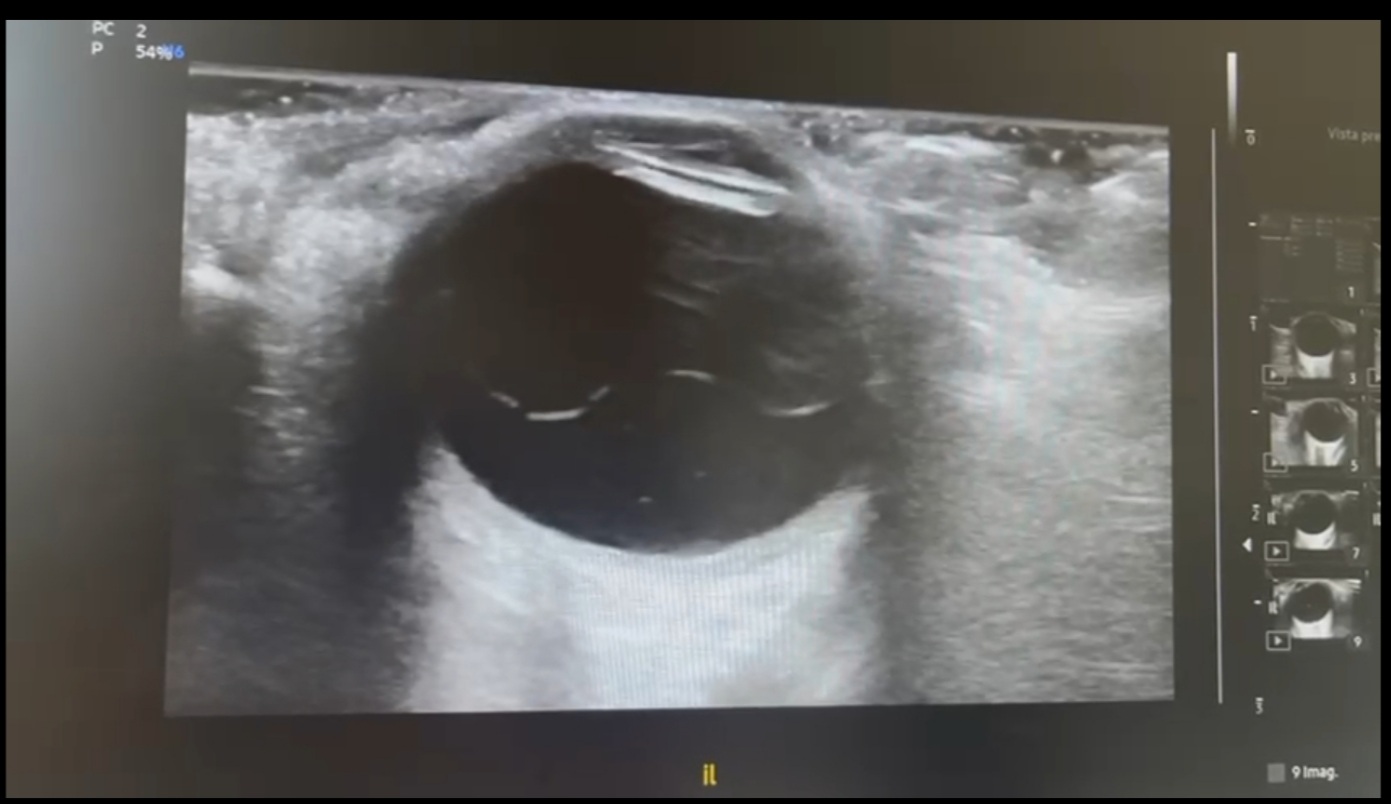

La ecografía ocular clínica en consulta, sonda lineal apoyando la sonda sin presionar, ojo cerrado, abundante gel, reducción de la potencia manteniendo atención al índice térmico y mecánico. Mostró una lámina hiperecogénica móvil en polo posterior, no originada en el nervio óptico (cuya distancia de vaina del nervio óptico menor de 5 mm), con bamboleo marcado a la maniobra dinámica (signo de la 'lavadora') y abundantes ecos móviles difusos en vítreo (aportaré video de maniobra dinámica).

El desprendimiento de vítreo posterior (DVP) suele mostrar una membrana hiperecogénica fina, libre. El desprendimiento de retina (DR) que nace de la papila en forma de "V" hacia periferia. En cambio, en el desprendimiento de retina regmatógeno (DRR), la lámina puede no nacer de papila, anclaje bilateral y movimiento ondulante y acompañado de hemorragia vítrea, como se evidenció.